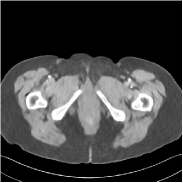

IV-F3 SUPER with only a Supervised Regularizer

This special case of SUPER corresponds to the case where SUPER excludes the unsupervised regularizer, while only involves the data-fidelity and a supervised regularizer in the MBIR cost, i.e., β=0𝛽0\beta=0 and μ0𝜇0\mu\neq 0. In this case, the proposed SUPER model is similar to a generalized block coordinate descent-based network by replacing a simple denoising autoencoder [28, 29, 30] with a general CNN that forms our supervised regularizer. This SUPER is also similar to the plug-and-play ADMM-Net method except that the inputs to each supervised network are the preceding reconstructions, while plug-and-play ADMM-Net updates inputs to the network (denoiser) based on auxiliary variables in the ADMM algorithm. Here, we used μ=1×106𝜇1superscript106\mu=1\times 10^{6}, which worked well for the plug-and-play ADMM-Net method, for this special case of SUPER. Fig. 7 shows a comparison between plug-and-play ADMM-Net, SUPER without unsupervised regularizers (in both training and testing), and the full SUPER version with ULTRA regularization (β=5×103𝛽5superscript103\beta=5\times 10^{3}, μ=5×105𝜇5superscript105\mu=5\times 10^{5}). All these methods used WavResNet as their denoisers/supervised networks. In this example, SUPER with only a supervised regularizer (SUPER-WRN-β=0𝛽0\beta=0) outperforms the plug-and-play ADMM-Net (ADMM-Net (WRN)) by 1.6 HU RMSE and provides sharper image details. Comparing SUPER-WRN-β=0𝛽0\beta=0 and the full SUPER-WRN-ULTRA scheme, we observe that the latter provides a lower RMSE and higher contrast image features than the former that excludes the unsupervised component. This again shows the effect of the unsupervised ULTRA model (in capturing local image details better with a union of learned transforms) in the SUPER scheme.

Figure 7: Reconstructed images of L192 slice 150 with WavResNet plugged ADMM-Net, SUPER-WRN-β=0𝛽0\beta=0 (both training and testing), and SUPER-WRN-ULTRA (β=5×103𝛽5superscript103\beta=5\times 10^{3} in both training and testing), respectively, shown with the reference image.